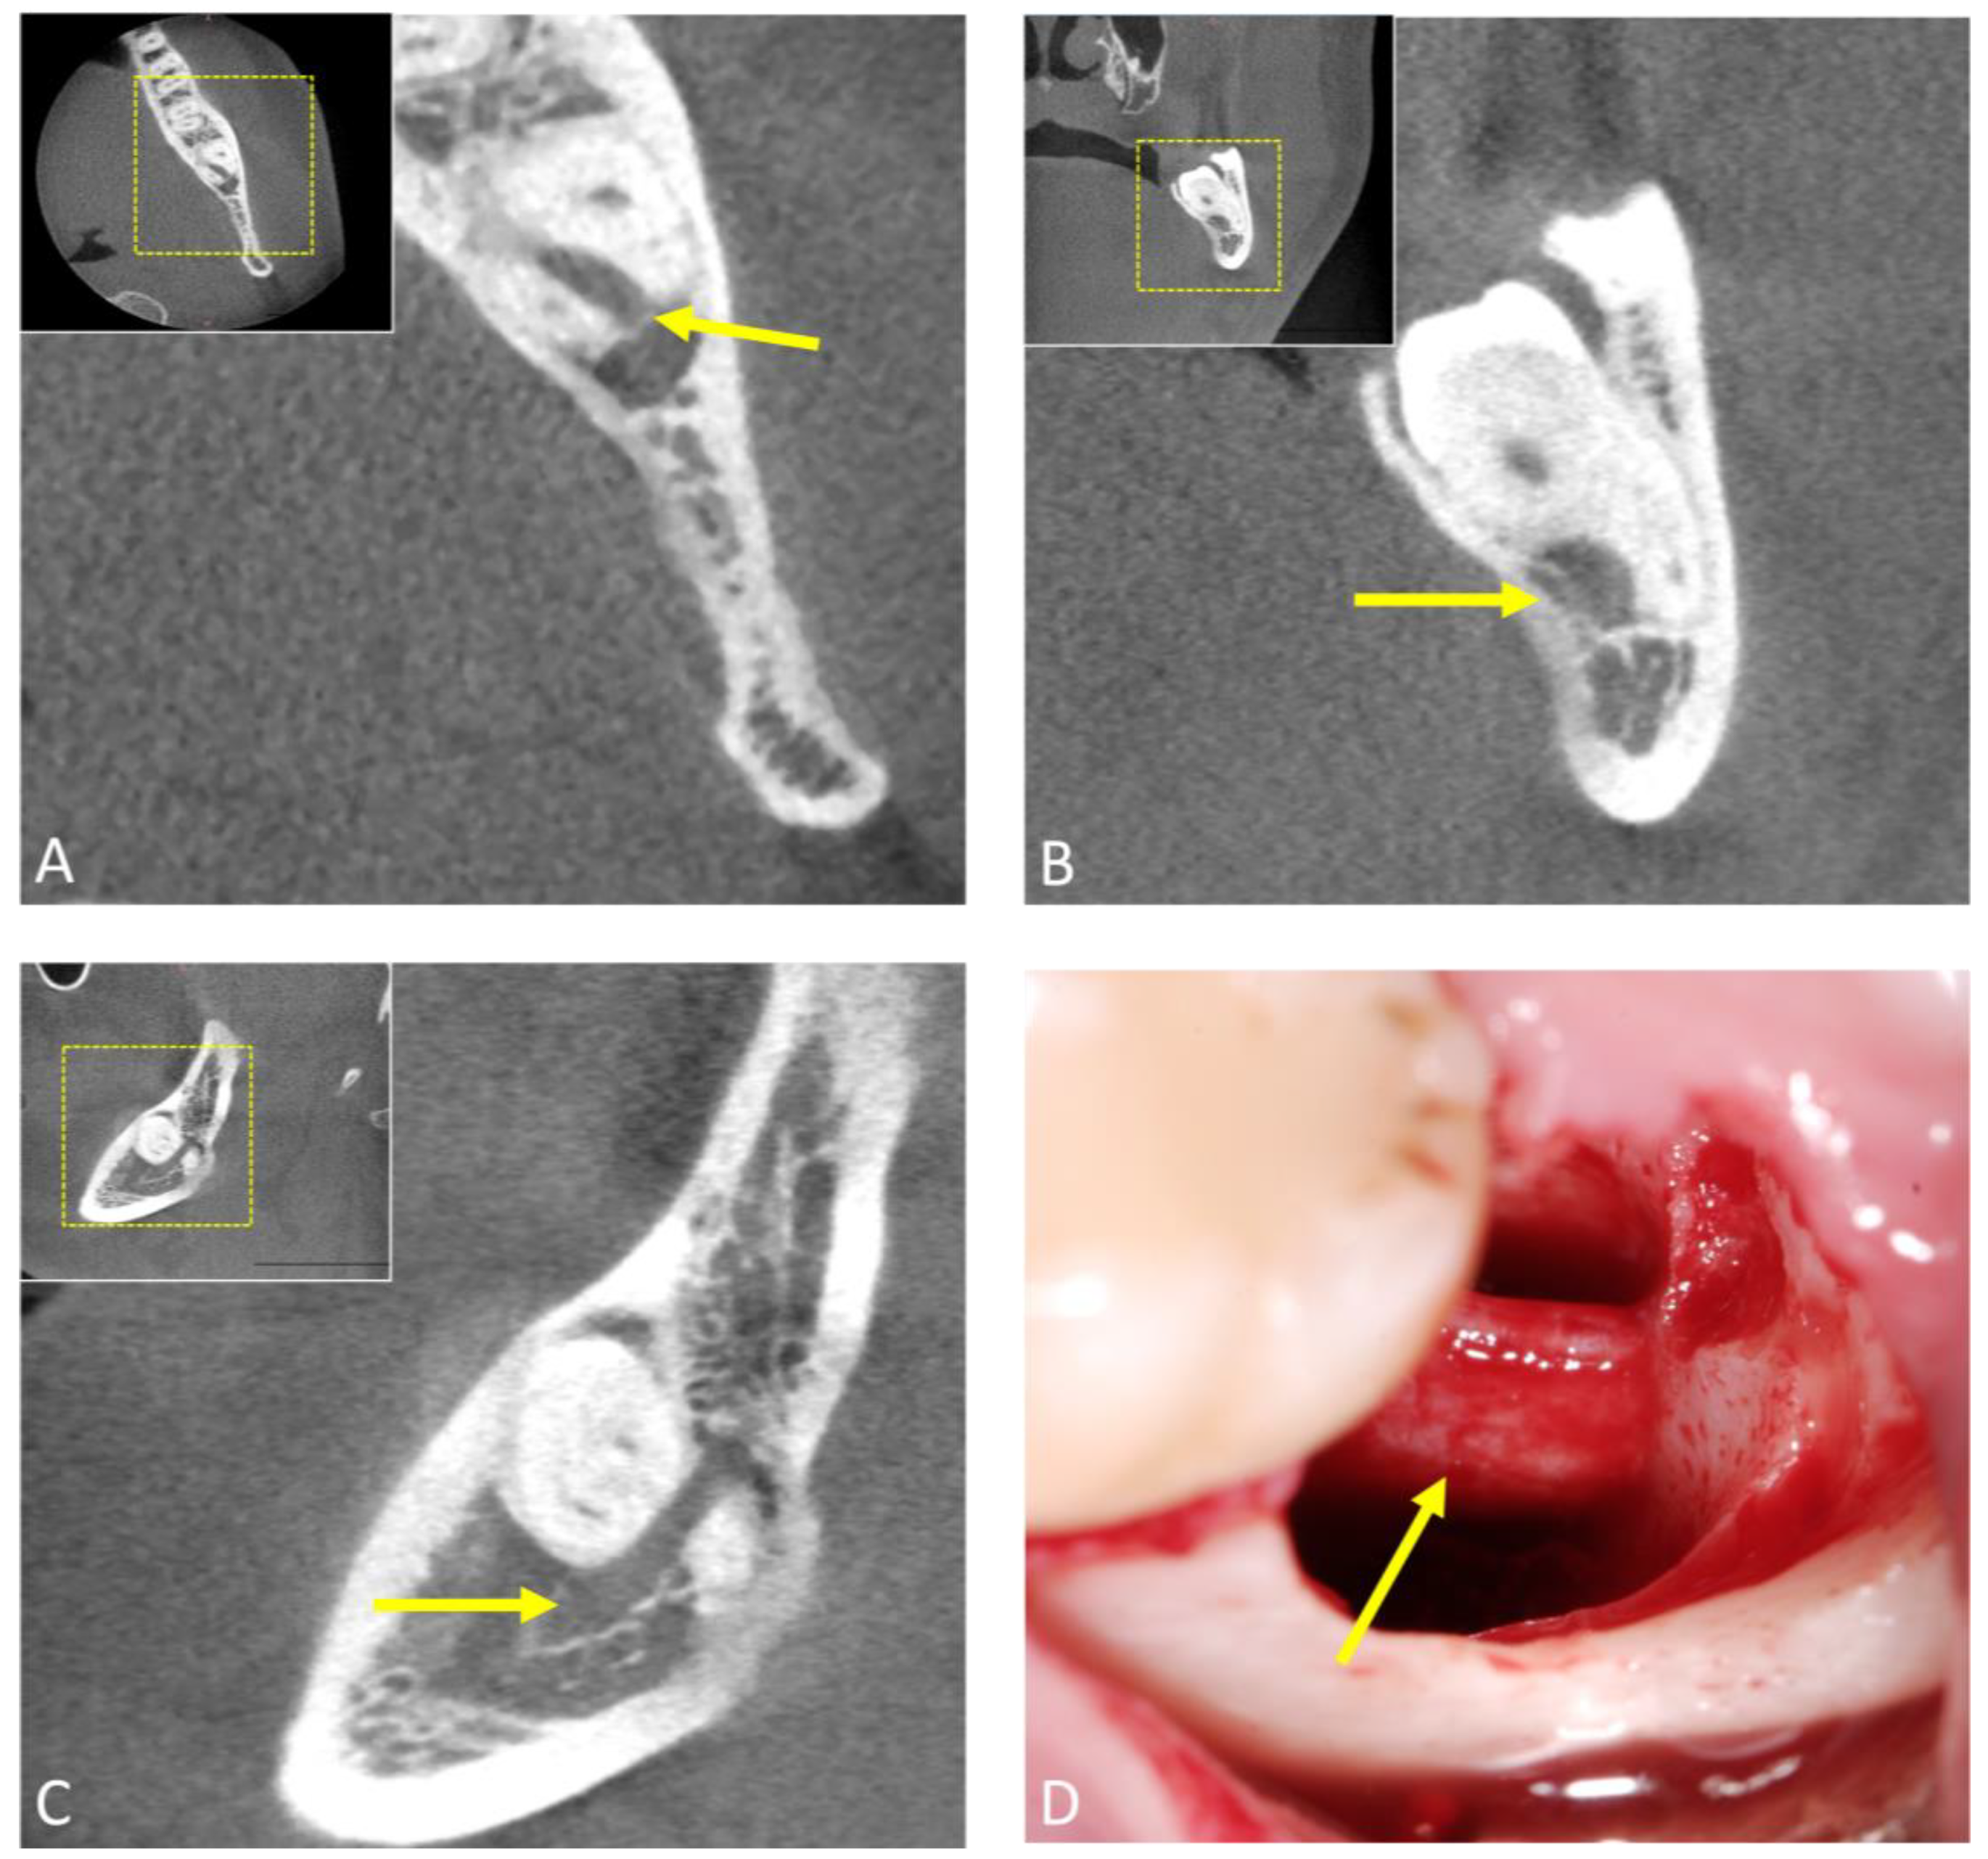

- Al-Haj Husain, A.; Stadlinger, B.; Winklhofer, S.; Müller, M.; Piccirelli, M.; Valdec, S. Mandibular Third Molar Surgery: Intraosseous Localization of the Inferior Alveolar Nerve Using 3D Double-Echo Steady-State MRI (3D-DESS). Diagnostics 2021, 11, 1245. [Google Scholar] [CrossRef] [PubMed]

- Al-Haj Husain, A.; Valdec, S.; Stadlinger, B.; Rucker, M.; Piccirelli, M.; Winklhofer, S. Preoperative visualization of the lingual nerve by 3D double-echo steady-state MRI in surgical third molar extraction treatment. Clin. Oral Investig. 2022, 26, 2043–2053. [Google Scholar] [CrossRef]

- Valdec, S.; Al-Haj Husain, A.; Winklhofer, S.; Müller, M.; Piccirelli, M.; Stadlinger, B. Comparison of Preoperative Cone-Beam Computed Tomography and 3D-Double Echo Steady-State MRI in Third Molar Surgery. J. Clin. Med. 2021, 10, 4768. [Google Scholar] [CrossRef]